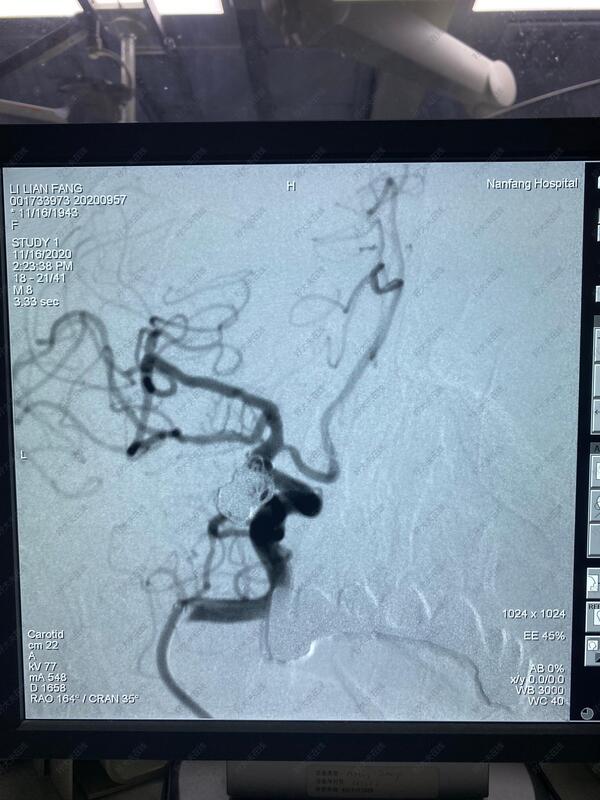

左侧后交通大型动脉瘤

治疗前

患者78岁高龄,颅内大型动脉瘤,随时有破裂出血死亡的风险,采用微创血管内介入治疗,填塞动脉瘤,保护正常血管